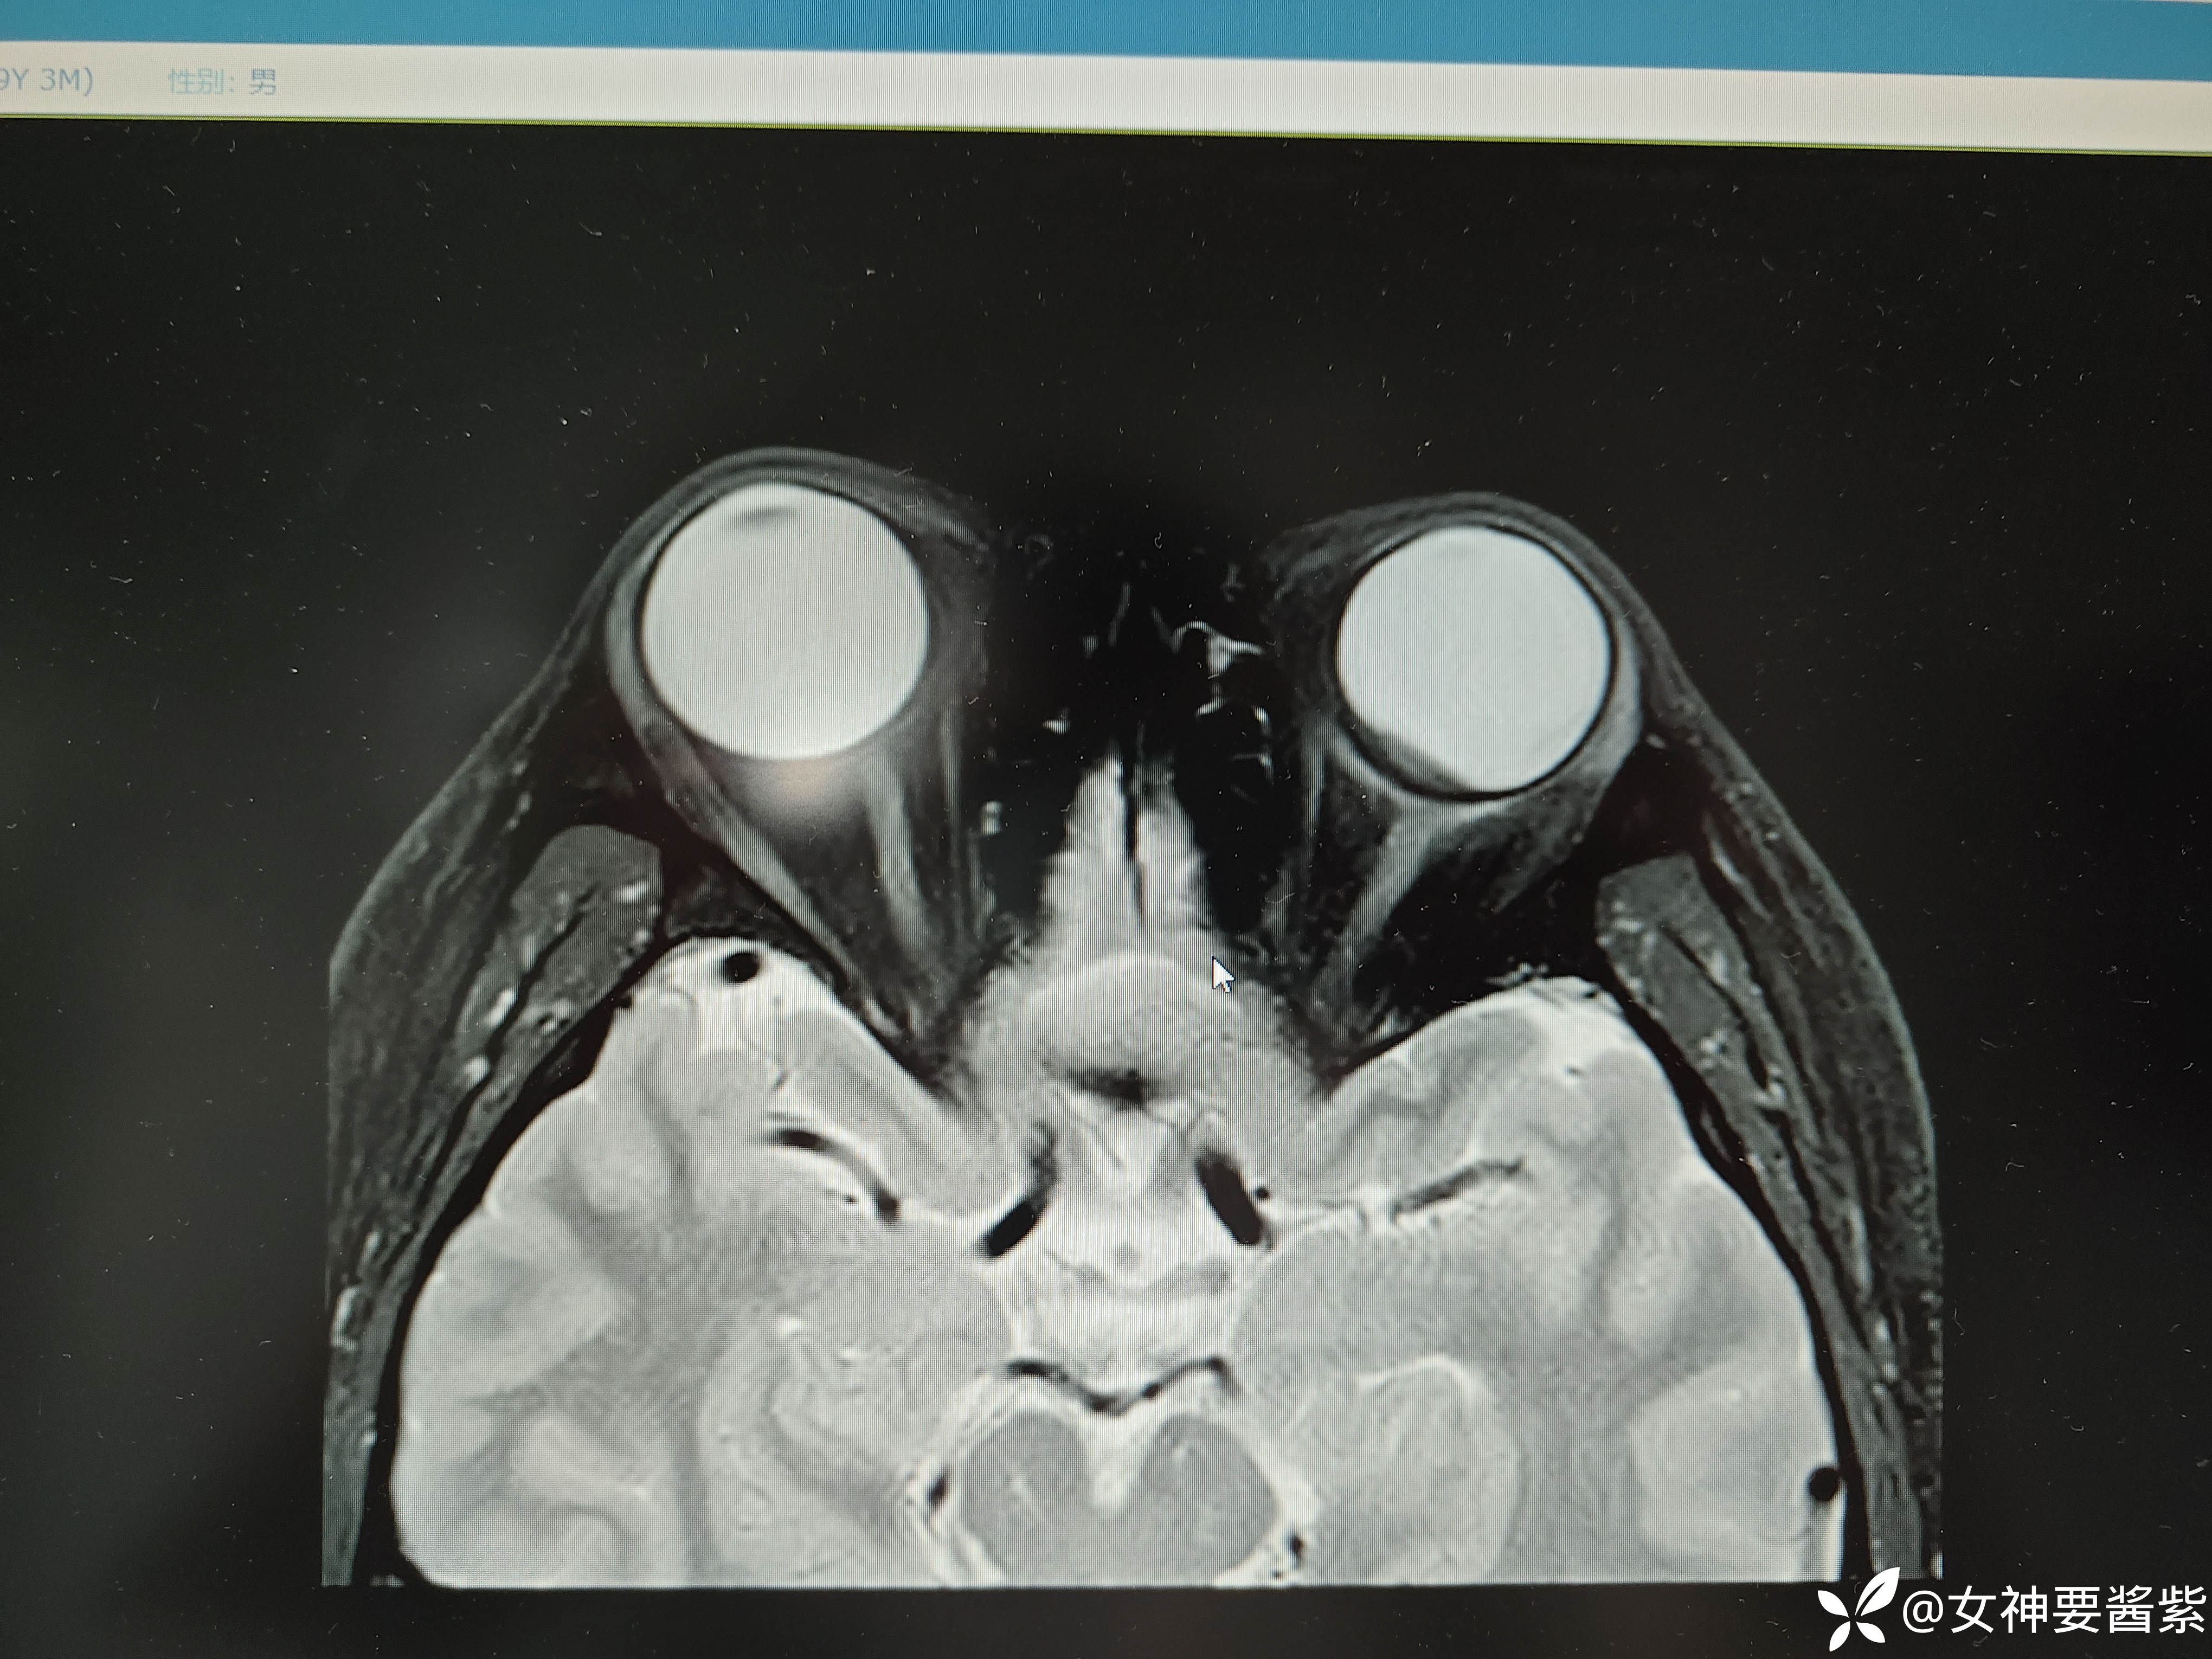

MR